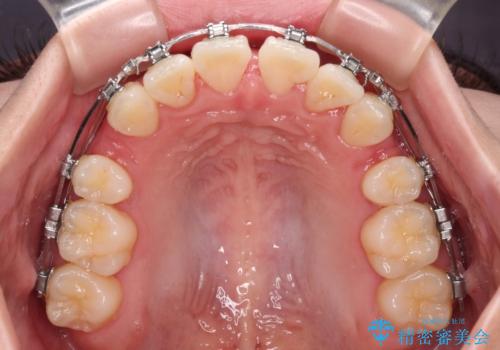

- 矯正装置

- メタルブラケット

- 1年10ヶ月

- 前歯がくちばしのように飛び出していることを気にして来院された患者様です。

唇が前方に突出している横顔が気になっているため、上下左右の第一小臼歯4本を抜歯し、ワイヤー装置にて矯正治療を行うこととしました。